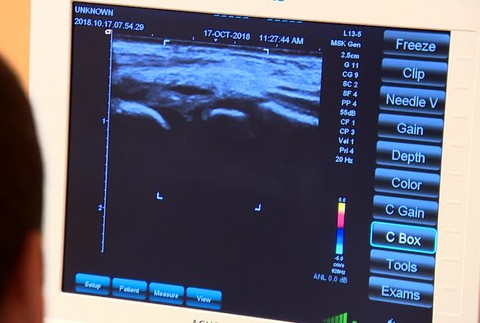

BRATISLAVA / Národný ústav detských chorôb v Bratislave má ako jeden z prvých špeciálny mobilný sonograf, ktorý dostal do daru.

Znamená to bezpečnejšiu diagnostiku malých pacientov, ide o prenosnú bezkáblovú technológiu, ľahšie sa ovláda a má lepšiu kvalitu obrazu. Vďaka bezkáblovým sondám je možné malého pacienta vyšetriť priamo na lôžku či operačnej sále. Čo lekári ale oceňujú najviac, je uľahčenie sonografického vyšetrenia u tých najmenších priamo v inkubátore

"Do inkubátoroch nepotrebujeme tieto káble sterilizovať, či dezinfikovať. To je tá najväčšia výhoda," hovorí primár rádiologického oddelenia Dušan Haviar.